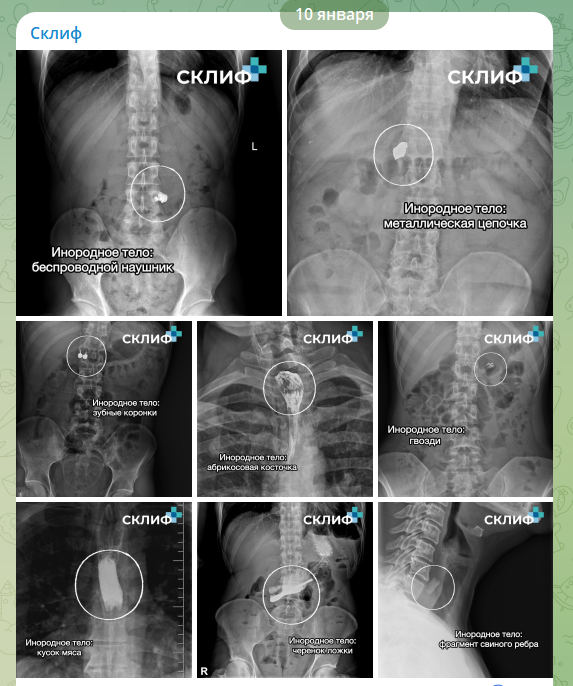

В "Склифе" показали на рентгене самые неожиданные находки в телах пациентов

В числе извлечённых предметов оказались не только современные гаджеты, но и предметы быта, а также детали, используемые при ремонте.

Врачи московского НИИ скорой помощи имени Склифосовского рассказали о самых необычных предметах, которые пришлось извлекать из пациентов в прошедшем году. Публикация с соответствующими рентгеновскими снимками появилась 10 января в официальном Telegram-канале медучреждения.

Согласно сообщению пресс-службы института, в числе находок 2025 года оказались беспроводные наушники, ювелирные украшения, зубные коронки и даже строительные гвозди. Последние, как отметили медики, пациенты нередко зажимали в зубах во время ремонта и случайно проглатывали. Помимо этого, в списке упоминаются абрикосовая косточка, черенок от ложки и фрагмент свиного ребра.

Представители НИИ подчеркнули, что за внешней необычностью отдельных случаев скрывается серьёзная медицинская проблема. Каждый год десятки людей доставляются в институт с инородными телами, застрявшими в пищеварительном тракте. Ситуация часто требует неотложного хирургического вмешательства, а последующая реабилитация может растянуться на длительный срок.

Основными причинами происшествий врачи называют бытовую невнимательность, особенно при работе с мелкими предметами, которые привычно держат во рту.

Медики обратились к гражданам с призывом проявлять большую осторожность в повседневной жизни.